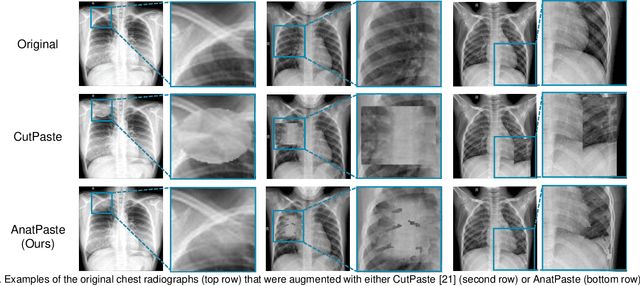

Abstract:Large numbers of labeled medical images are essential for the accurate detection of anomalies, but manual annotation is labor-intensive and time-consuming. Self-supervised learning (SSL) is a training method to learn data-specific features without manual annotation. Several SSL-based models have been employed in medical image anomaly detection. These SSL methods effectively learn representations in several field-specific images, such as natural and industrial product images. However, owing to the requirement of medical expertise, typical SSL-based models are inefficient in medical image anomaly detection. We present an SSL-based model that enables anatomical structure-based unsupervised anomaly detection (UAD). The model employs the anatomy-aware pasting (AnatPaste) augmentation tool. AnatPaste employs a threshold-based lung segmentation pretext task to create anomalies in normal chest radiographs, which are used for model pretraining. These anomalies are similar to real anomalies and help the model recognize them. We evaluate our model on three opensource chest radiograph datasets. Our model exhibit area under curves (AUC) of 92.1%, 78.7%, and 81.9%, which are the highest among existing UAD models. This is the first SSL model to employ anatomical information as a pretext task. AnatPaste can be applied in various deep learning models and downstream tasks. It can be employed for other modalities by fixing appropriate segmentation. Our code is publicly available at: https://github.com/jun-sato/AnatPaste.